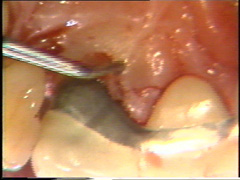

Visión palatina: Eliminación del tejido de granulación.

En las zonas dónde están las lesiones de furcación es dificil su limpieza: Puede utilizarse instrumental de mano, ultrasonido y a veces debe modificar la anatomía de la lesión para mejorar la higiene postoperatoria. Esto lo puede llevar a cavo con instrumental rotatorio (puntas de diamante) a baja velocidad y abundante refrigeración acuosa.

Ningún método parece ser superior al otro cuando evaluamos  el resultado curativo clínico.